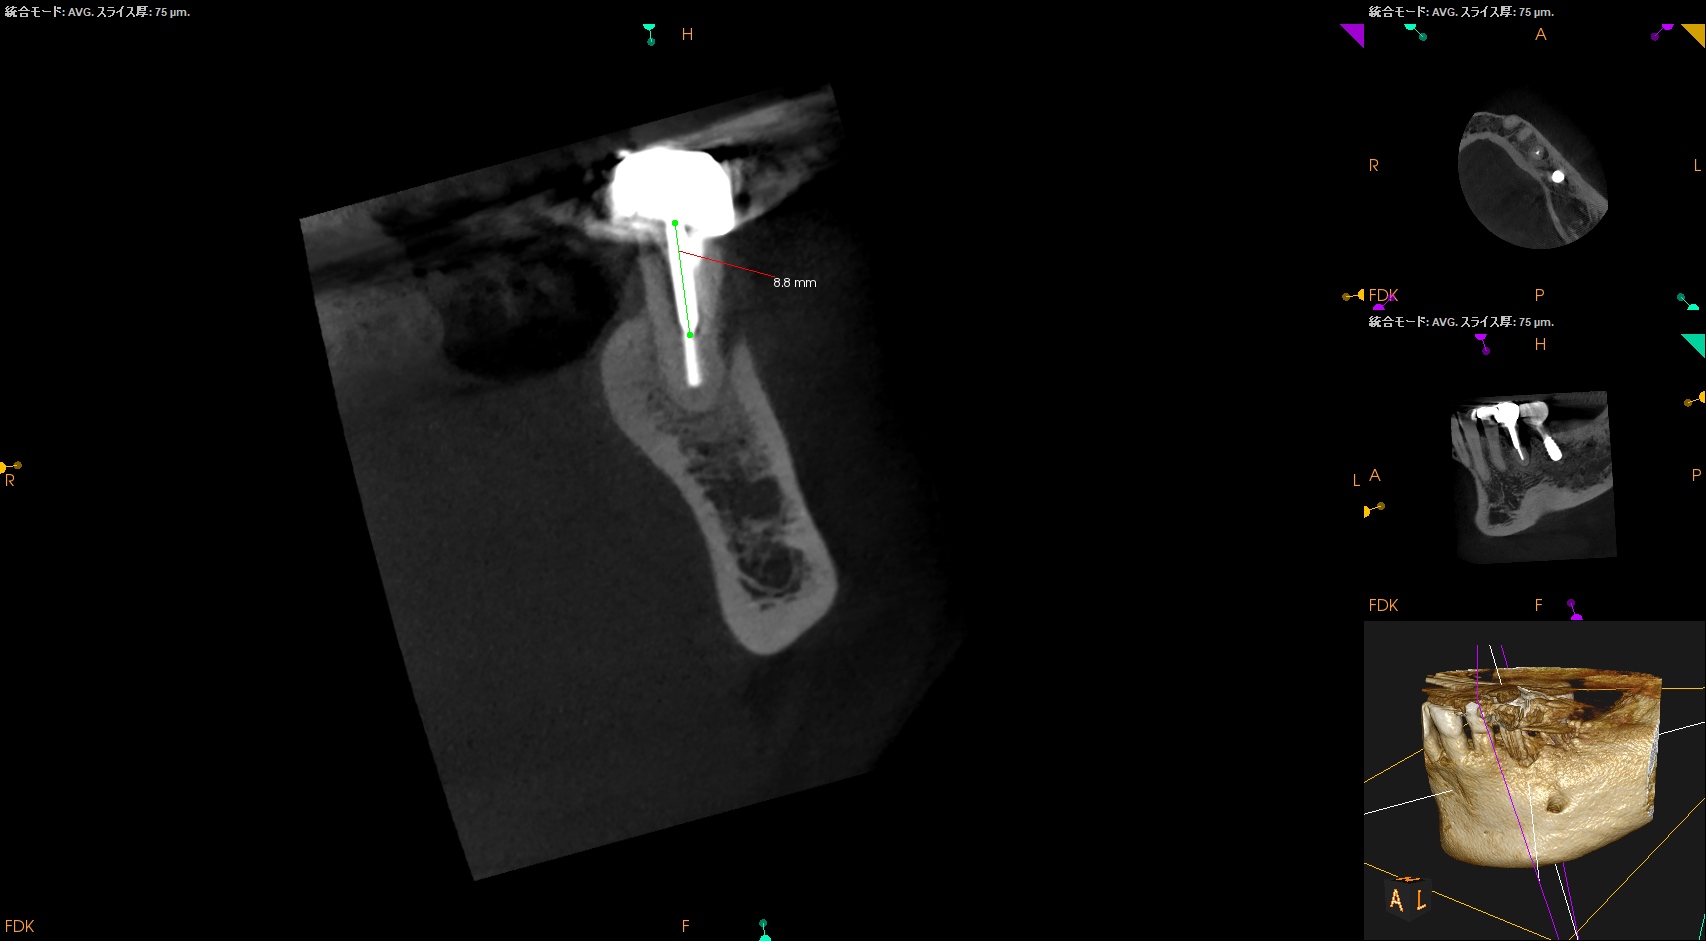

今回のケースであれば、

8.8mm…

まさにこのケースがそれに該当する。

スクリューピンの除去には相当時間がかかるとわかる。